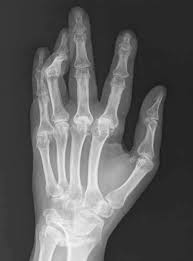

류마티스관절염은 초기에는 피로감, 미열, 전신 근골격 통증이 동반될 수 있고, 손가락, 발가락 등의 관절 마디가 붓는다고 한다.

병이 진행되면 다발성으로 여러 관절이 동시에 붓고, 자는 동안 악화돼 아침에 일어나면 한 시간 이상 뻣뻣하고 부기가 가라앉지 않는다고 한다.